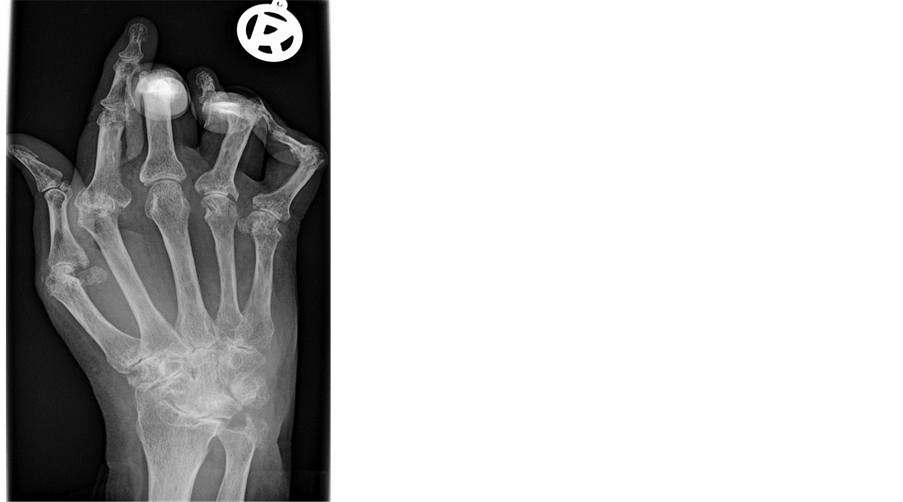

Arthritis Osteoarthritis (OA) ppt download

From slideplayer.com

Arthritis Osteoarthritis (OA) ppt download Rheumatoid Arthritis Eyes Burning Ra can affect your eyes in many different ways, some of which might be more serious than others. Scleritis can cause eye redness and pain, whereas sjögren's syndrome. Since ra is an autoimmune disease, it can attack the collagen in the sclera and cornea, causing severe inflammation. It can occur as a. Rheumatoid arthritis can cause eye complications such as. Rheumatoid Arthritis Eyes Burning.